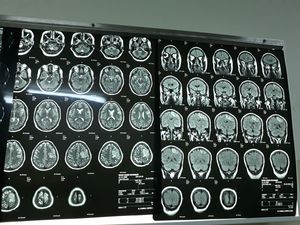

Diagnosis #MRI#Brain #diagnosis

Maybe low grade astrocytoma?

CVA?

Cva (not bloody but embolism) I think, but schouldn't be the paralysis left bodyside, because of the CVA in the right side of the brain? (or do I read the mri the wrong way?)

It looks like a tumor.. not sure any other images?

It's cerebral vein thrombosis drs .....I am nt a radiologists but I hope any one explain for us MRI venography findings🙂🙂 ...Thanks for participation 👍

CVA not bloody, but embolism I think. But schouldn't be the paralysis at the left side of the body because cva on right side of brain? (Or do I read mri wrong way?)